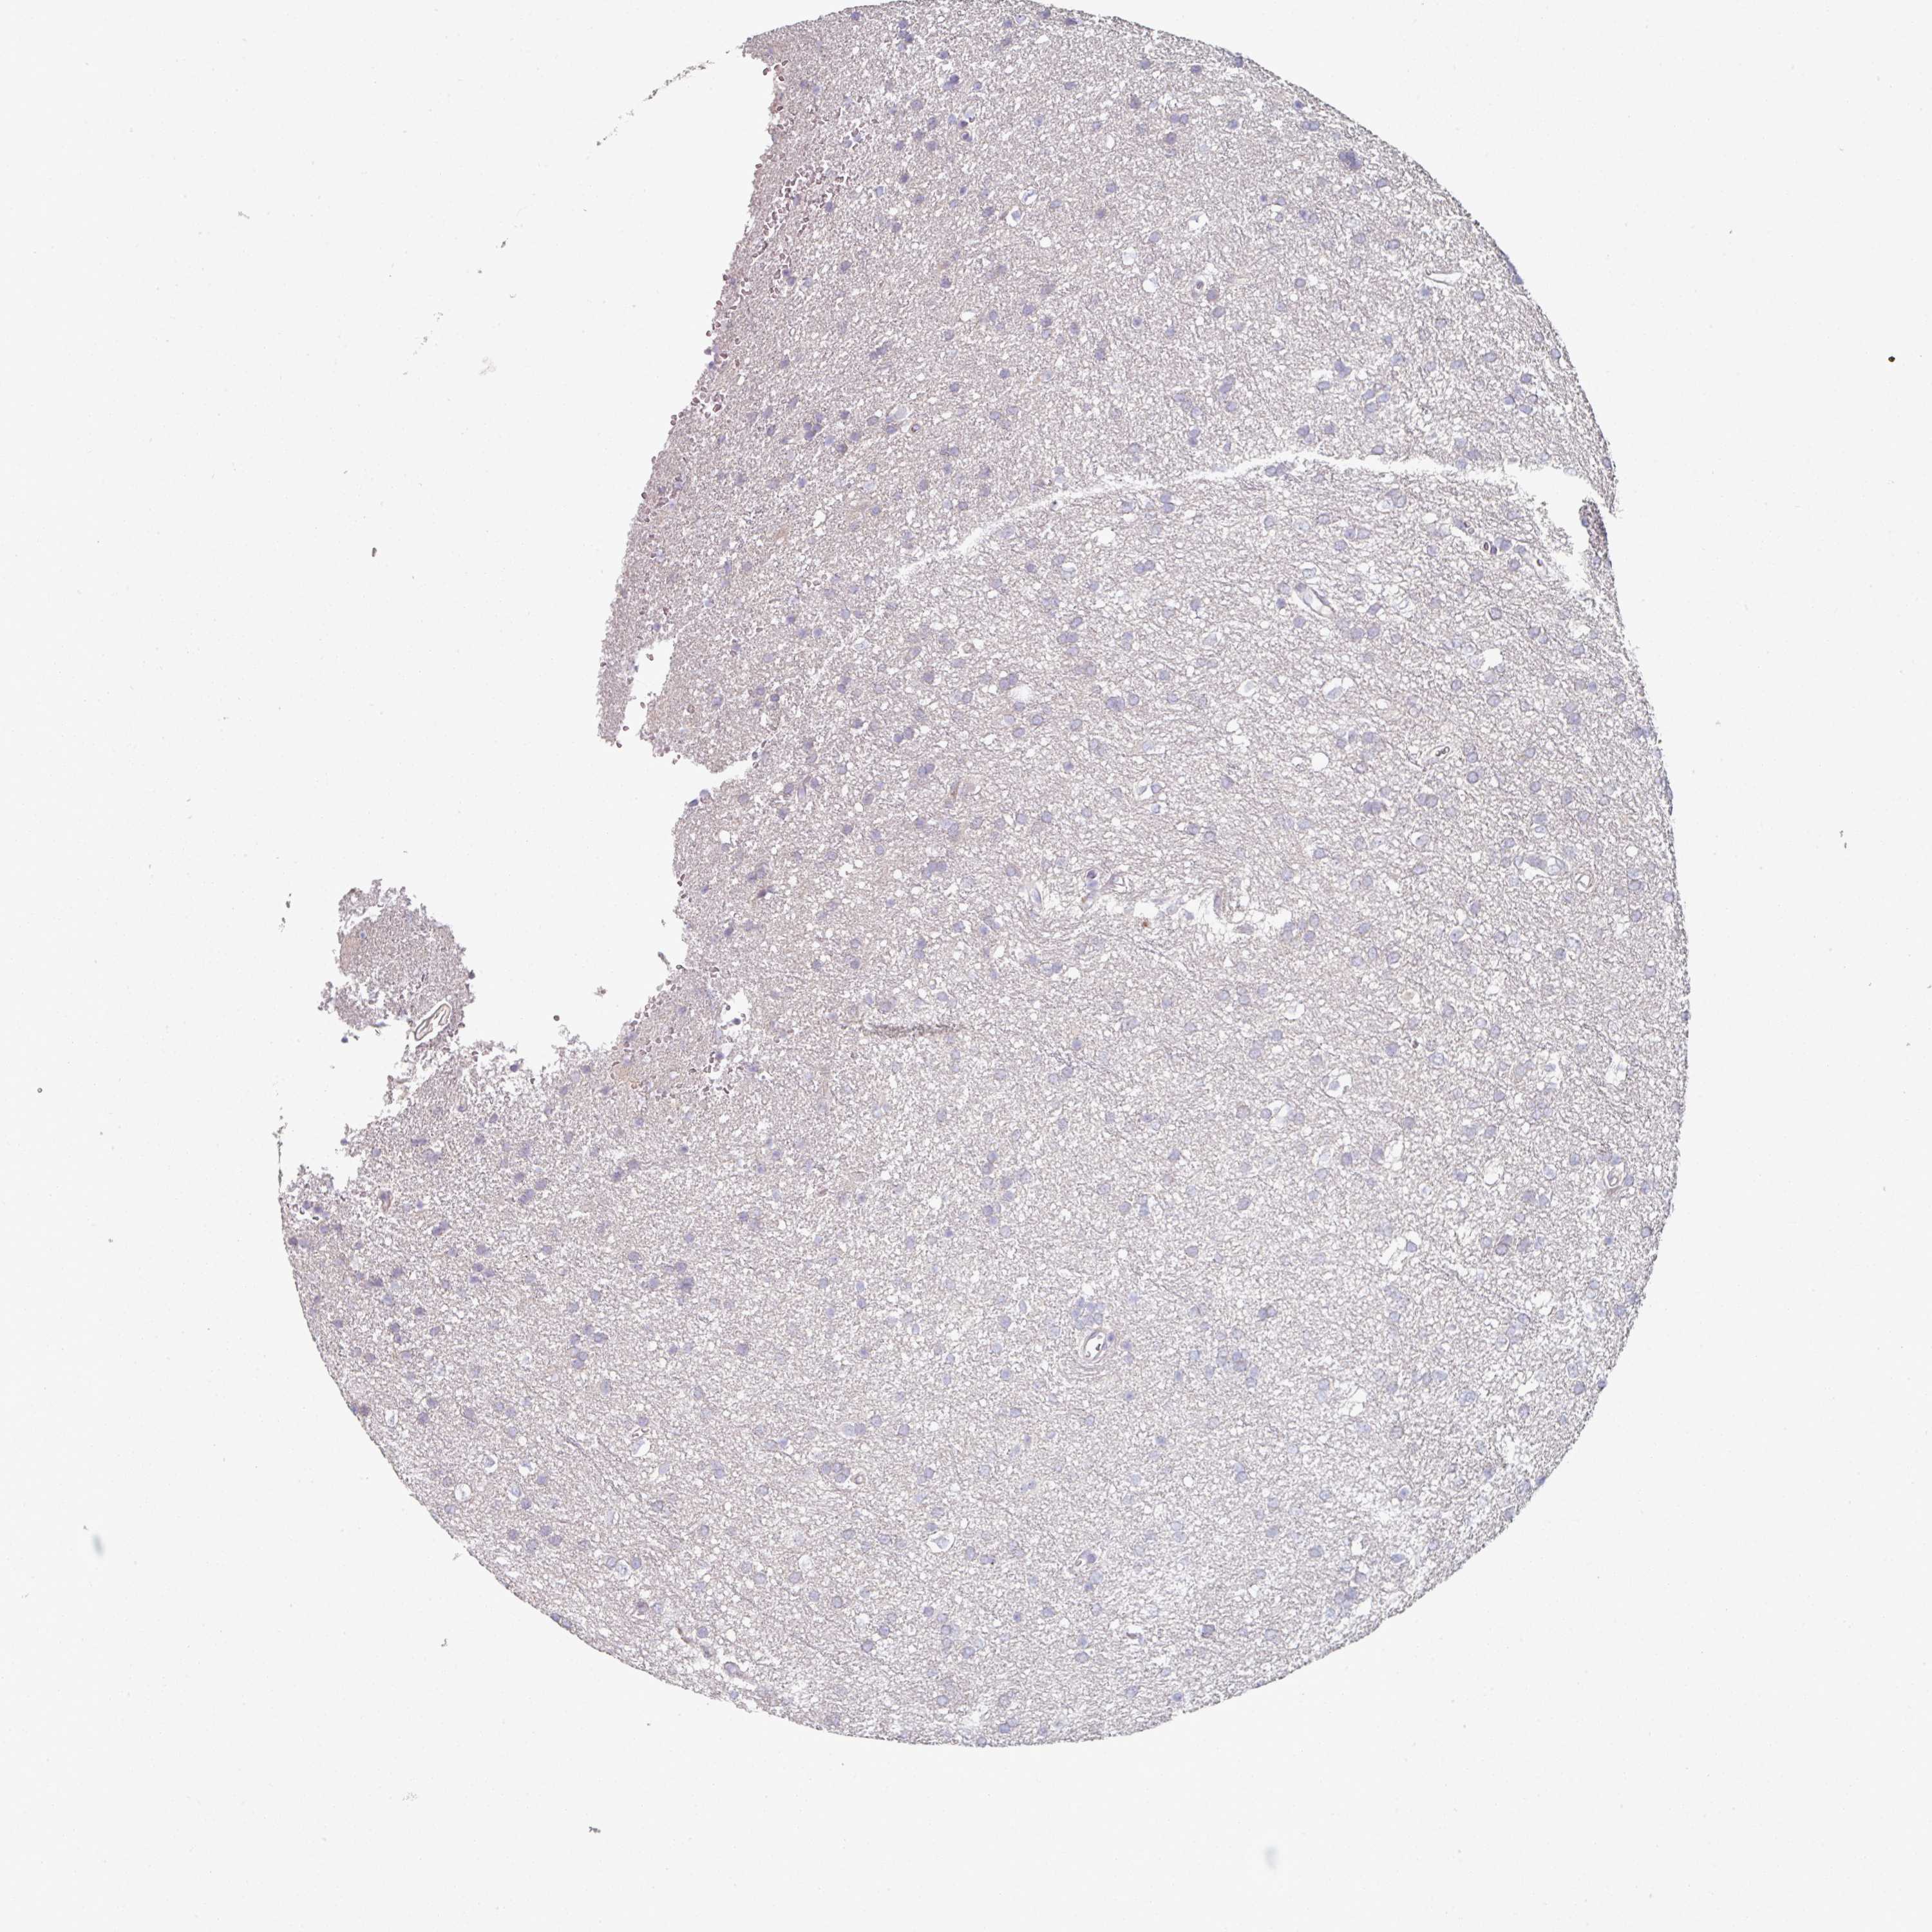

GLIOMA - Protein expressioni

A mouse-over function shows sample information and annotation data. Click on an image to view it in a full screen mode. Samples can be filtered based on level of antibody staining by selecting one or several of the following categories: high, medium, low and not detected. The assay and annotation is described here.

Note that samples used for immunohistochemistry by the Human Protein Atlas do not correspond to samples in the TCGA dataset.

Antibody stainingi

Antibody staining in the annotated cell types in the current human tissue is reported as not detected, low, medium, or high, based on conventional immunohistochemistry profiling in selected tissues. This score is based on the combination of the staining intensity and fraction of stained cells.

Each image is clickable and will lead to virtual microscopy that enables deeper exploration of all samples and also displays staining intensity scores, fraction scores and subcellular localization as well as patient and tissue information for each sample.

Antibody HPA052606

Antibody HPA077139

Staining

High

Medium

Low

Not detected

Intensity

Strong

Moderate

Weak

Negative

Quantity

>75%

75%-25%

<25%

None

Location

Nuclear

Cytoplasmic/membranous

Cytoplasmic/membranous,nuclear

Glioma, malignant, Low grade

Glioma, malignant, High grade

Glioma, malignant, NOS